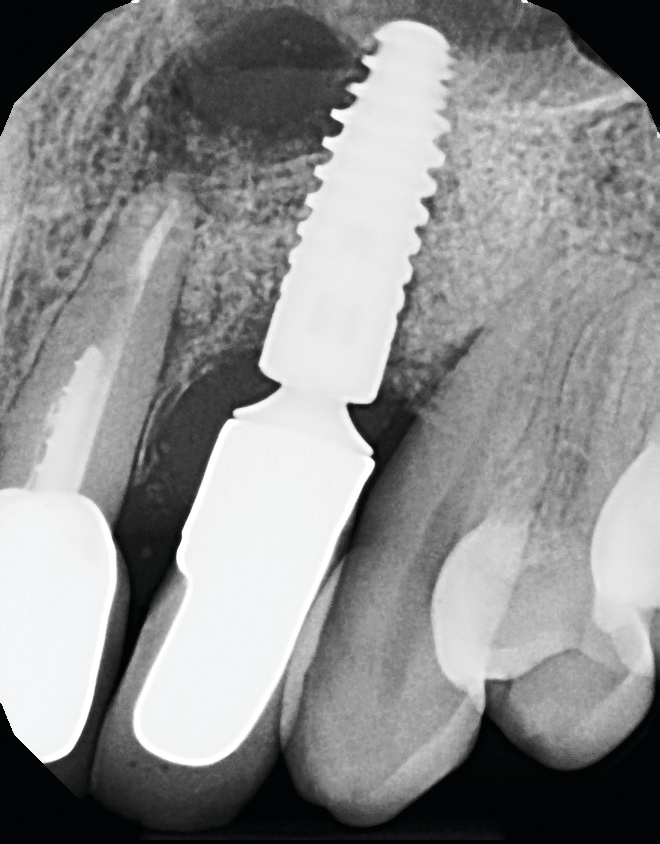

Implants can wear out eventually or without good oral hygiene. Dental implants are not suitable for everyone, few patients may not be eligible for tooth replacement due to their bone health. Dental implants generally require healthy, dense bones. Strong bones in place are a parameter to support dental implants.

In severe cases, your dentist usually needs to perform a bone graft procedure before replacing the faulty implant. Read also : Teeth Transplant. Bone grafting is a process in which new bone is grown.